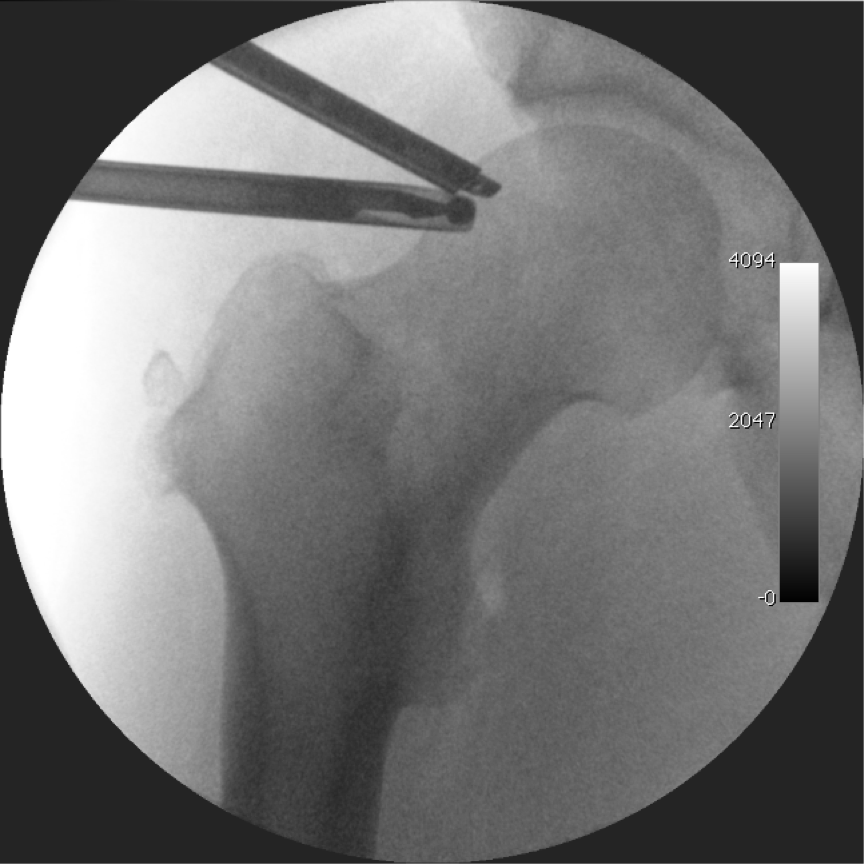

In order to perform the procedure, traction is applied to the operative leg with a. After hip arthroscopy the wound is covered with gauze or ace wraps. Do not hyperextend or hyperflex your hip.

A special type of boot applies traction to your foot, which separates the ball and socket of the hip joint. With hip arthroscopy, there is a small chance of numbness in the genitalia, inner thigh, and top of the foot briefly postoperatively. Some pain and tightness may be experienced around the incision sites on the hip.

The open joint, also called joint distraction, allows a surgeon to introduce the arthroscope into your joint. The next phase of physio; Perform 30 reps of this motion.